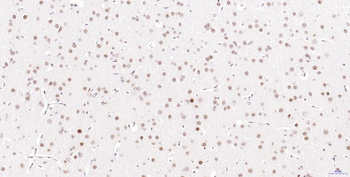

100 μl, 50 μl, 25 μl - Rad51 Recombinant Rabbit Monoclonal Antibody [orb608069]Featured

IF, IHC-Fr, IHC-P, WB

Human, Mouse, Rat

Mouse, Rat

Rabbit

Recombinant

Unconjugated

50 μl, 100 μl - KLF4 Recombinant Rabbit Monoclonal Antibody [orb608075]Featured